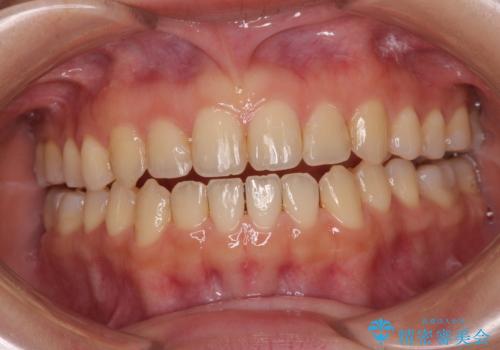

前歯のオープンバイト インビザラインで咬み合わせを改善

- 前歯の開咬を気にして来院された患者様です。

開咬の治療は、前歯を閉じるように動かすとともに、上下臼歯を圧下(骨内にめり込ませる)させることで進めて行きます。

インビザラインは臼歯の圧下を効果的に行えるため、インビザラインを用いて矯正治療を行うこととしました。